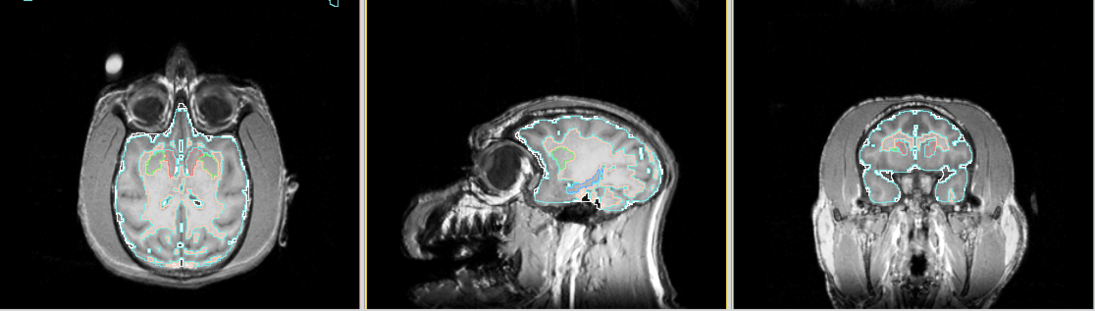

Segmentation results as in screen shots

View 1 : upper row - using Slicer 3.4 binary release; middle row - Slicer 3.4 build from source; lower row - using Slicer 2.6